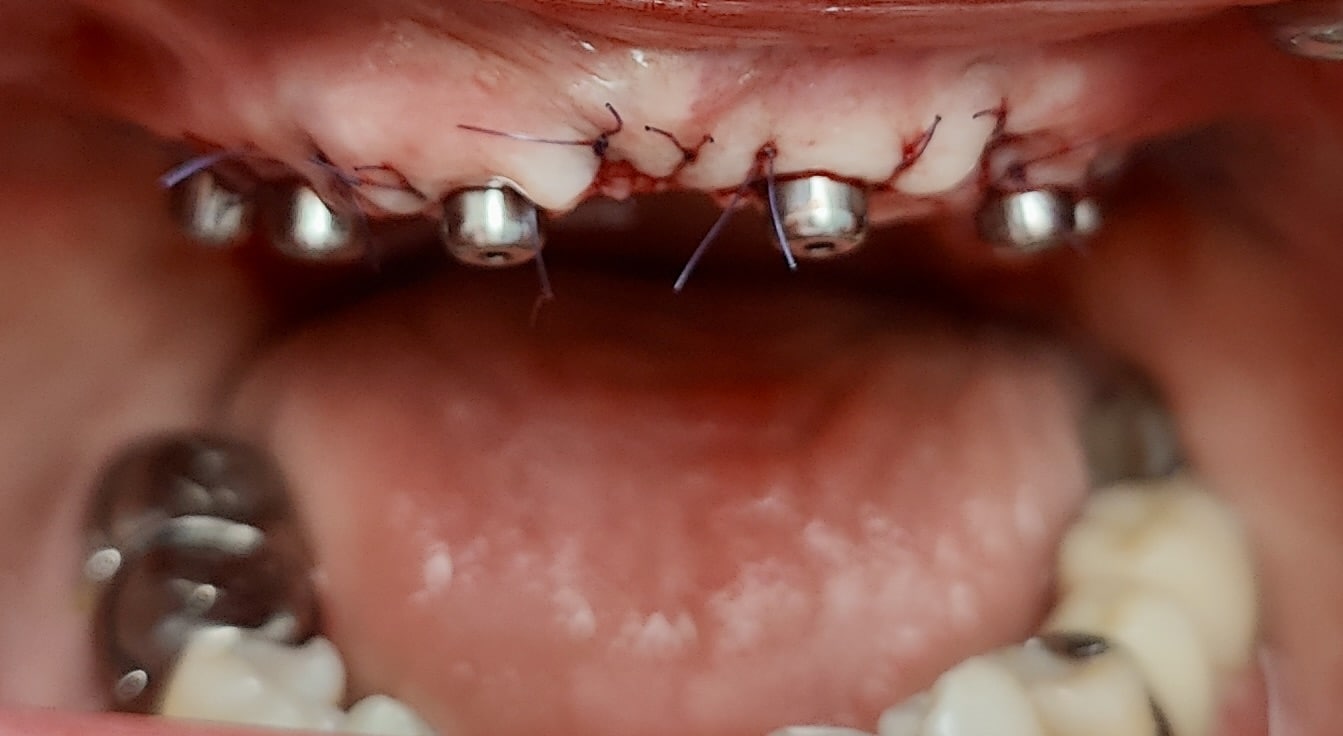

Vues cliniques le lendemain (au moment de la pose du bridge provisoire) :